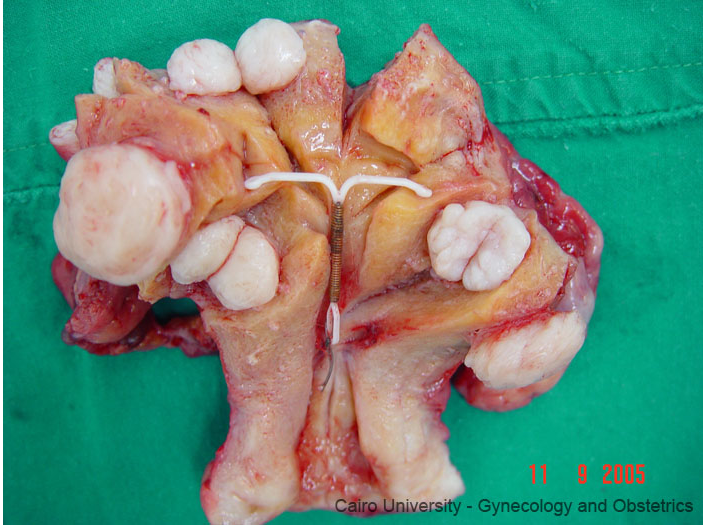

[ gambar yang ketumbuhan yang putih-putih dibawah ini adalah contoh fibroid ]